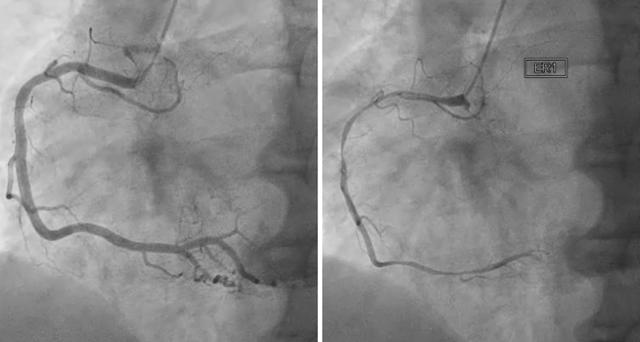

심장성형술과 스텐트 시술은 요골동맥이나 대퇴동맥을 통해 혈관이 막히거나 좁아진 곳을 찾아 혈관 조영술을 시행한 후 풍선과 스텐트라는 철망을 이용해 혈관에 카테터를 삽입해 혈관을 넓혀주는 시술입니다. 대부분의 병원에서 일주일 이내에 또는 빠르면 다음 날 퇴원할 수 있어요.